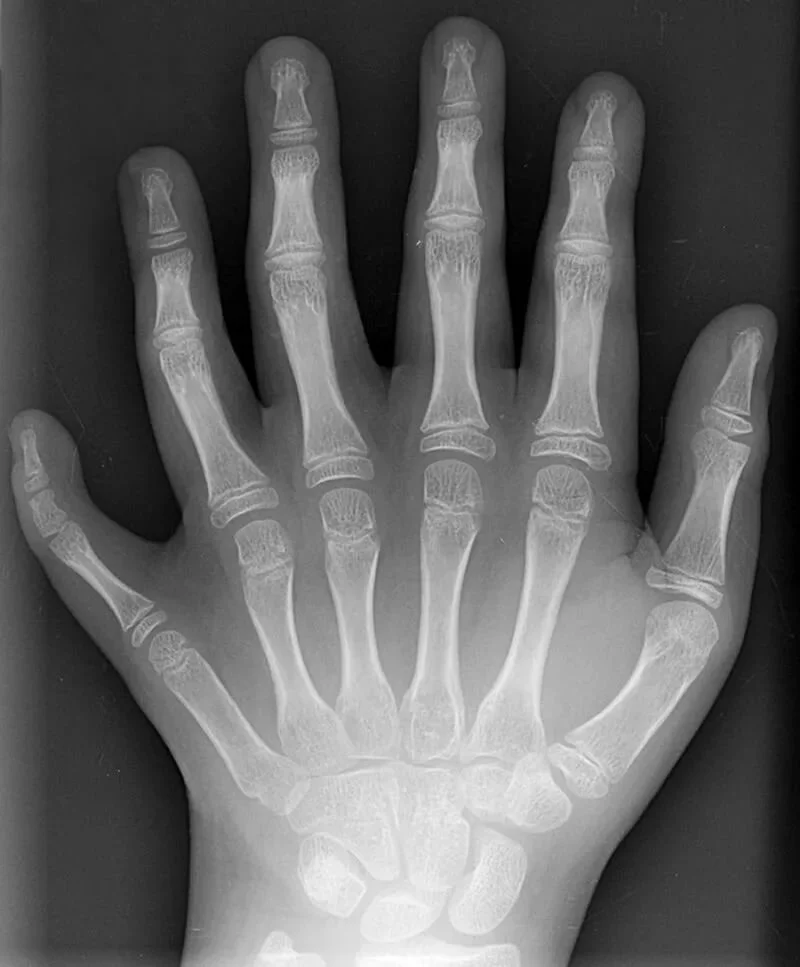

Полидактилия - наследственное заболевание а, причём довольно распространённое. Это заболевание выражается в том, что развивается дополнительные конечности, то есть, у будущей певицы на левой руке будет два больших пальца.

Снимок руки